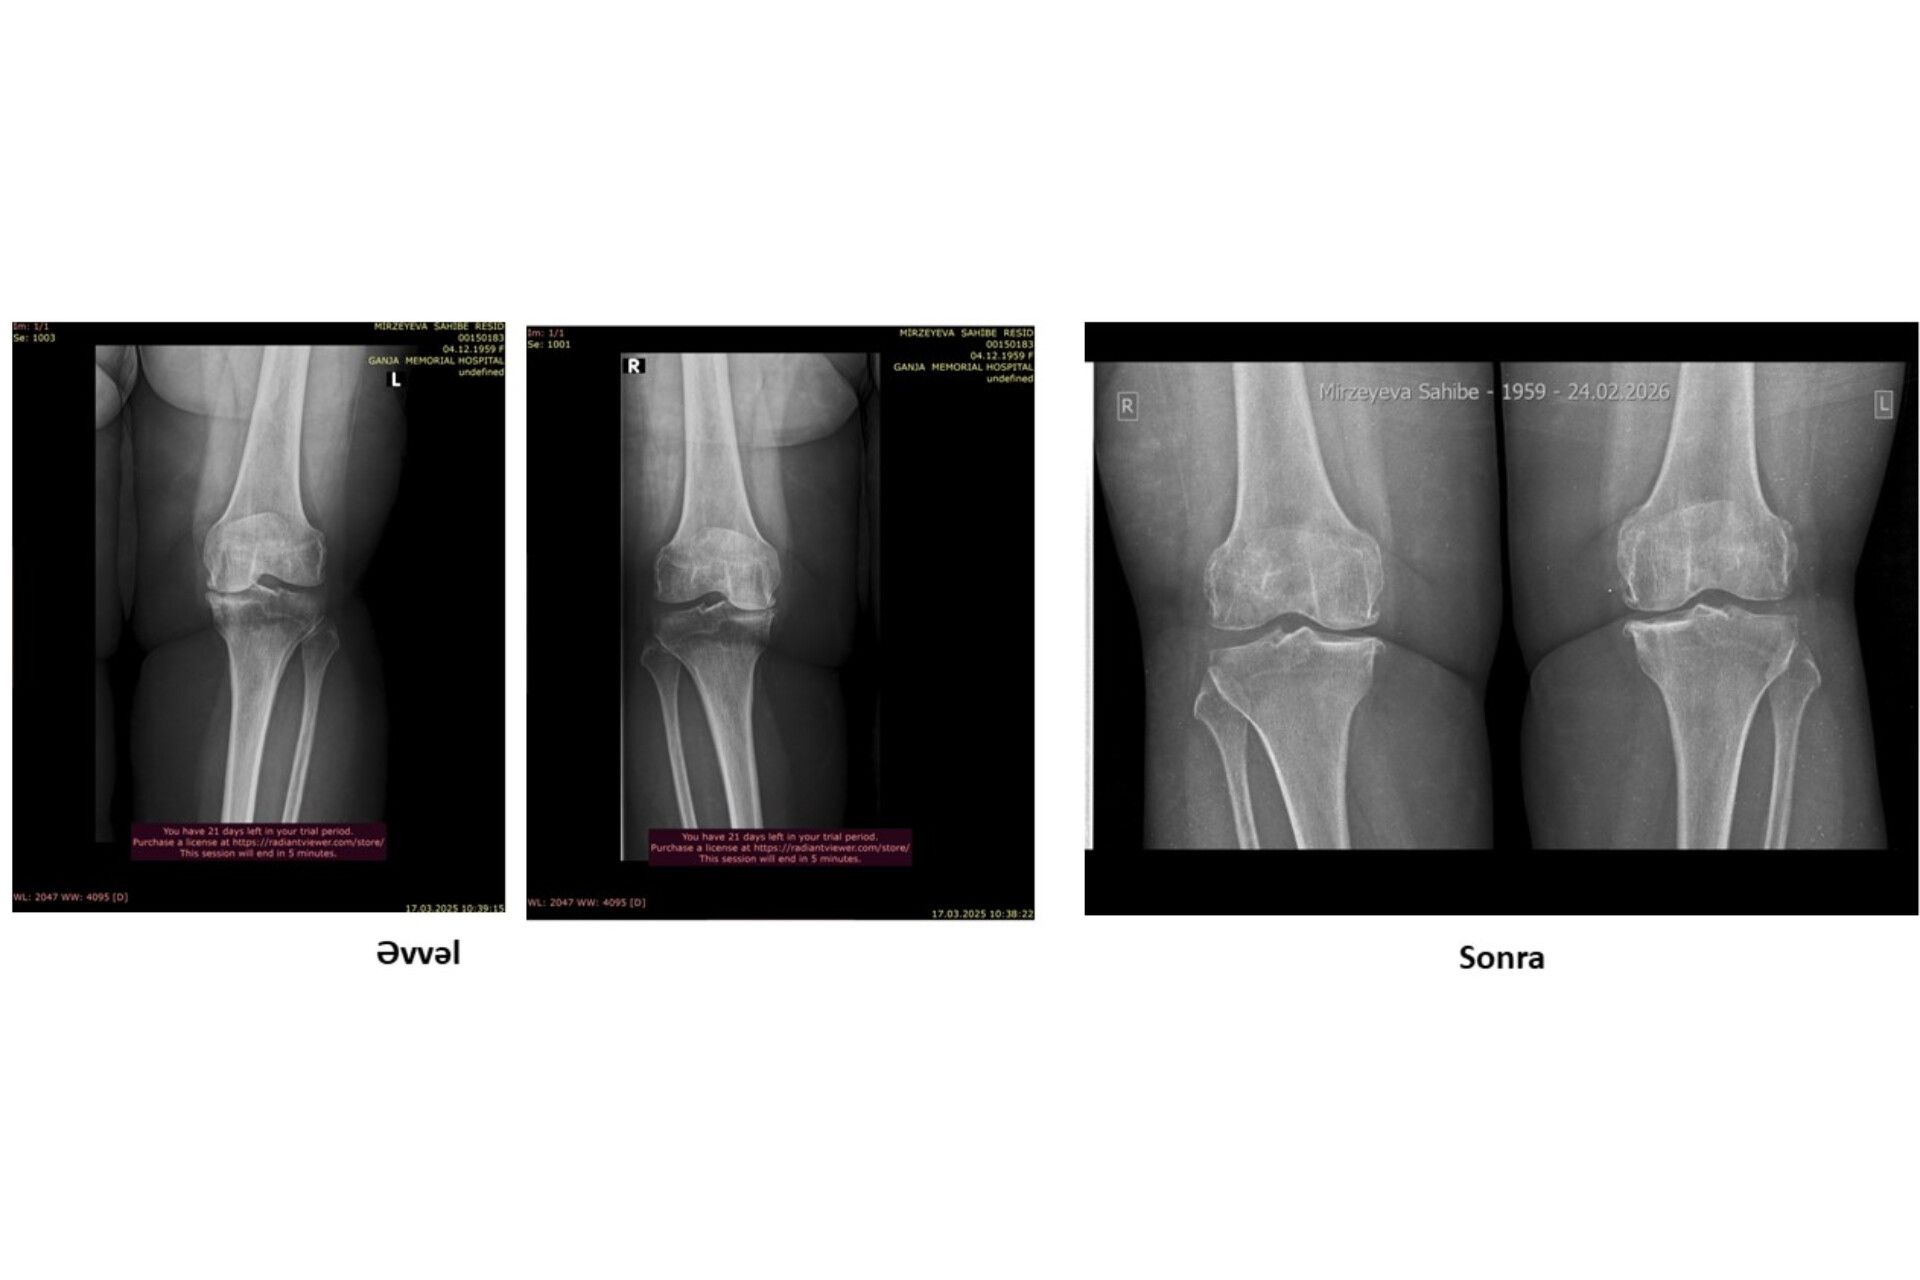

Protez təklif edildi, amma əməliyyatsız sağaldı –  Real pasiyent hekayəsi-VİDEO

Oynaqlarda yaranan artroz, xüsusilə də xəstəliyin 4-cü mərhələsi, tibbdə ən ağır vəziyyətlərdən biri hesab olunur. Bu mərhələdə xəstələrə əksər hallarda yeganə çıxış yolu kimi cərrahi əməliyyat – süni oynaq (protez) təklif edilir.

Lakin son illər bəzi klinikalarda tətbiq olunan inteqrativ yanaşmalar bu sahədə fərqli nəticələrin mümkün olduğunu göstərir.

Bioloji Təbabət İnteqrativ Müalicə Mərkəzinə müraciət edən pasiyentə 4-cü dərəcəli artroz diaqnozu qoyulmuşdu.

Pasiyent daha əvvəl müraciət etdiyi tibb müəssisələrində yalnız əməliyyatın mümkün çıxış yolu olduğu barədə məlumat almışdı. Güclü ağrılar, hərəkət məhdudiyyəti və gündəlik həyat keyfiyyətinin aşağı düşməsi onun əsas şikayətləri idi.

Nəticə: əməliyyata ehtiyac qalmadı

Aparılan müalicədən sonra pasiyentdə nəzərəçarpacaq müsbət dəyişikliklər müşahidə olunub:

• ağrılar əhəmiyyətli dərəcədə azalıb

• oynağın hərəkət qabiliyyəti yaxşılaşıb

• gündəlik fəaliyyətlər daha rahat icra olunmağa başlayıb

• həyat keyfiyyəti yüksəlib

Hazırkı vəziyyətdə pasiyent üçün cərrahi müdaxiləyə ehtiyac qalmadığı bildirilir.